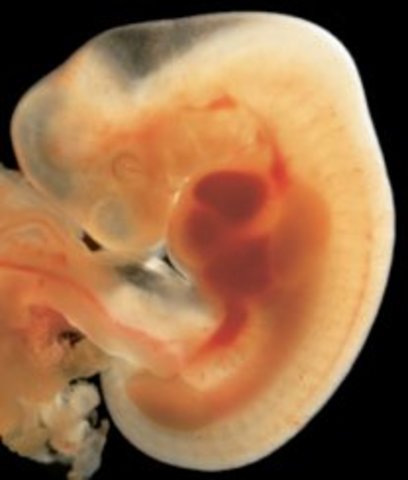

• Week Six: The Heart Begins to Beat

Week Six: The Heart Begins to Beat

Blood vessels and blood cells start to develope and a pipe shaped heart starts to form and beat. The brain is also divided into five parts.

• Week Seven: Arms and Legs Begin to Grow

Week Seven: Arms and Legs Begin to Grow

The baby's main organs are starting to developed as well as their arms and legs. The heart has now been divided into two chambers.

• Week Eight: Starts to Practice Moving

Week Eight: Starts to Practice Moving

The embryo is starting to practice moving. Mouth and teeth are also starting to from as well as facial features.